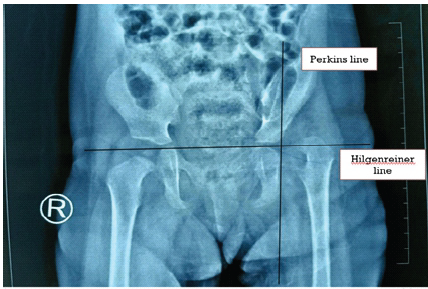

Hip disorders in the paediatric population (patients <16 years) represent a varied collection of conditions ranging from traumatic, developmental, infectious, neoplastic, and metabolic causes [1]. These pathologies, if not promptly diagnosed and treated, frequently result in long-term morbidity, including permanent deformities, chronic pain, gait abnormalities, and compromised quality of life in adulthood [1,2]. The unique developmental anatomy of the pediatric hip, characterized by the presence of a vulnerable physeal plate and changing vascular patterns, contributes to its susceptibility to specific age-related diseases [3]. Common non-traumatic paediatric hip disorders include developmental dysplasia of the hip (DDH) (Fig. 1), Legg-Calvé-Perthes disease (Perthes’) (Fig. 2 and 3), slipped capital femoral epiphysis (SCFE) (Fig. 4), and infective conditions such as septic arthritis (Fig. 5) and tubercular arthritis [3].

Figure 1: Image showing the small dysplastic femur head outside the shallow acetabulum cavity in upper outer quadrant.